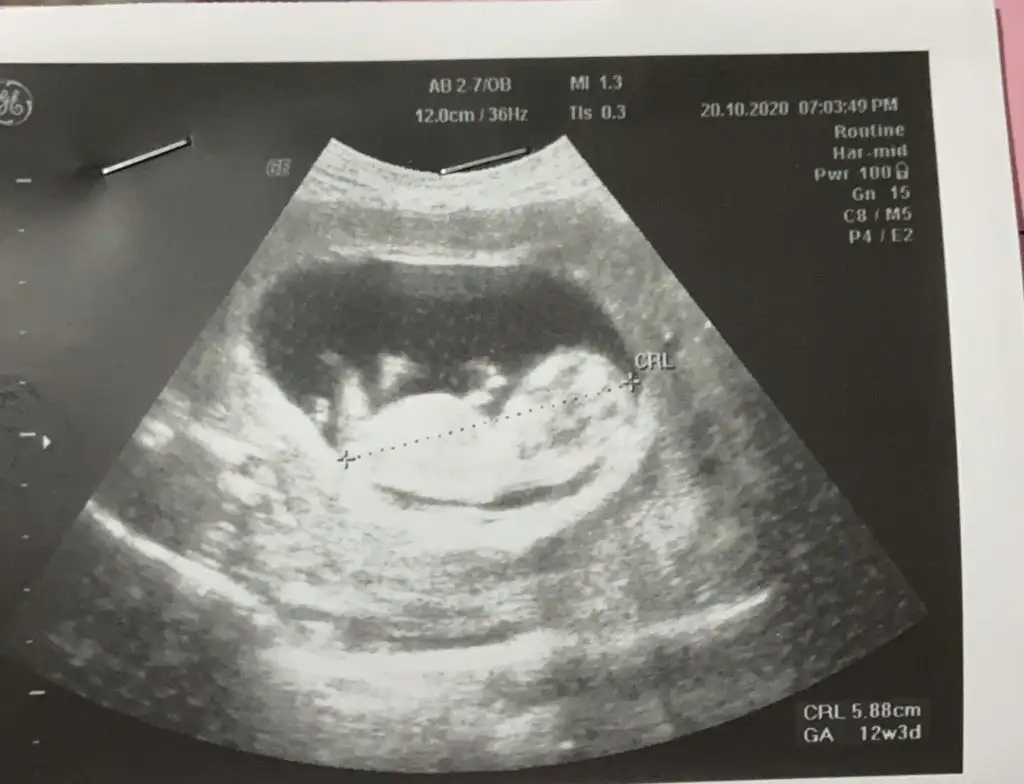

Şimdilik erkek gibi 12-13 hafta usgde paylasinZaten 11 hafta

Bu 12.hafta11 12 13 haftalar olmalı sanki kız gibi gibi istediğim haftalar varsa paylaşın

Kız gibi gibi sankiBu 12.haftaEki Görüntüle 2709157